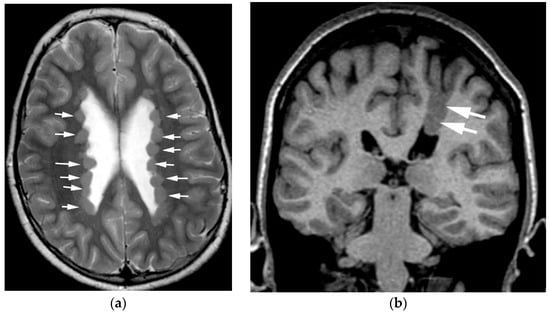

3.5. Agenesis of the Corpus Callosum

3.6. Hypogenesis of the Corpus Callosum